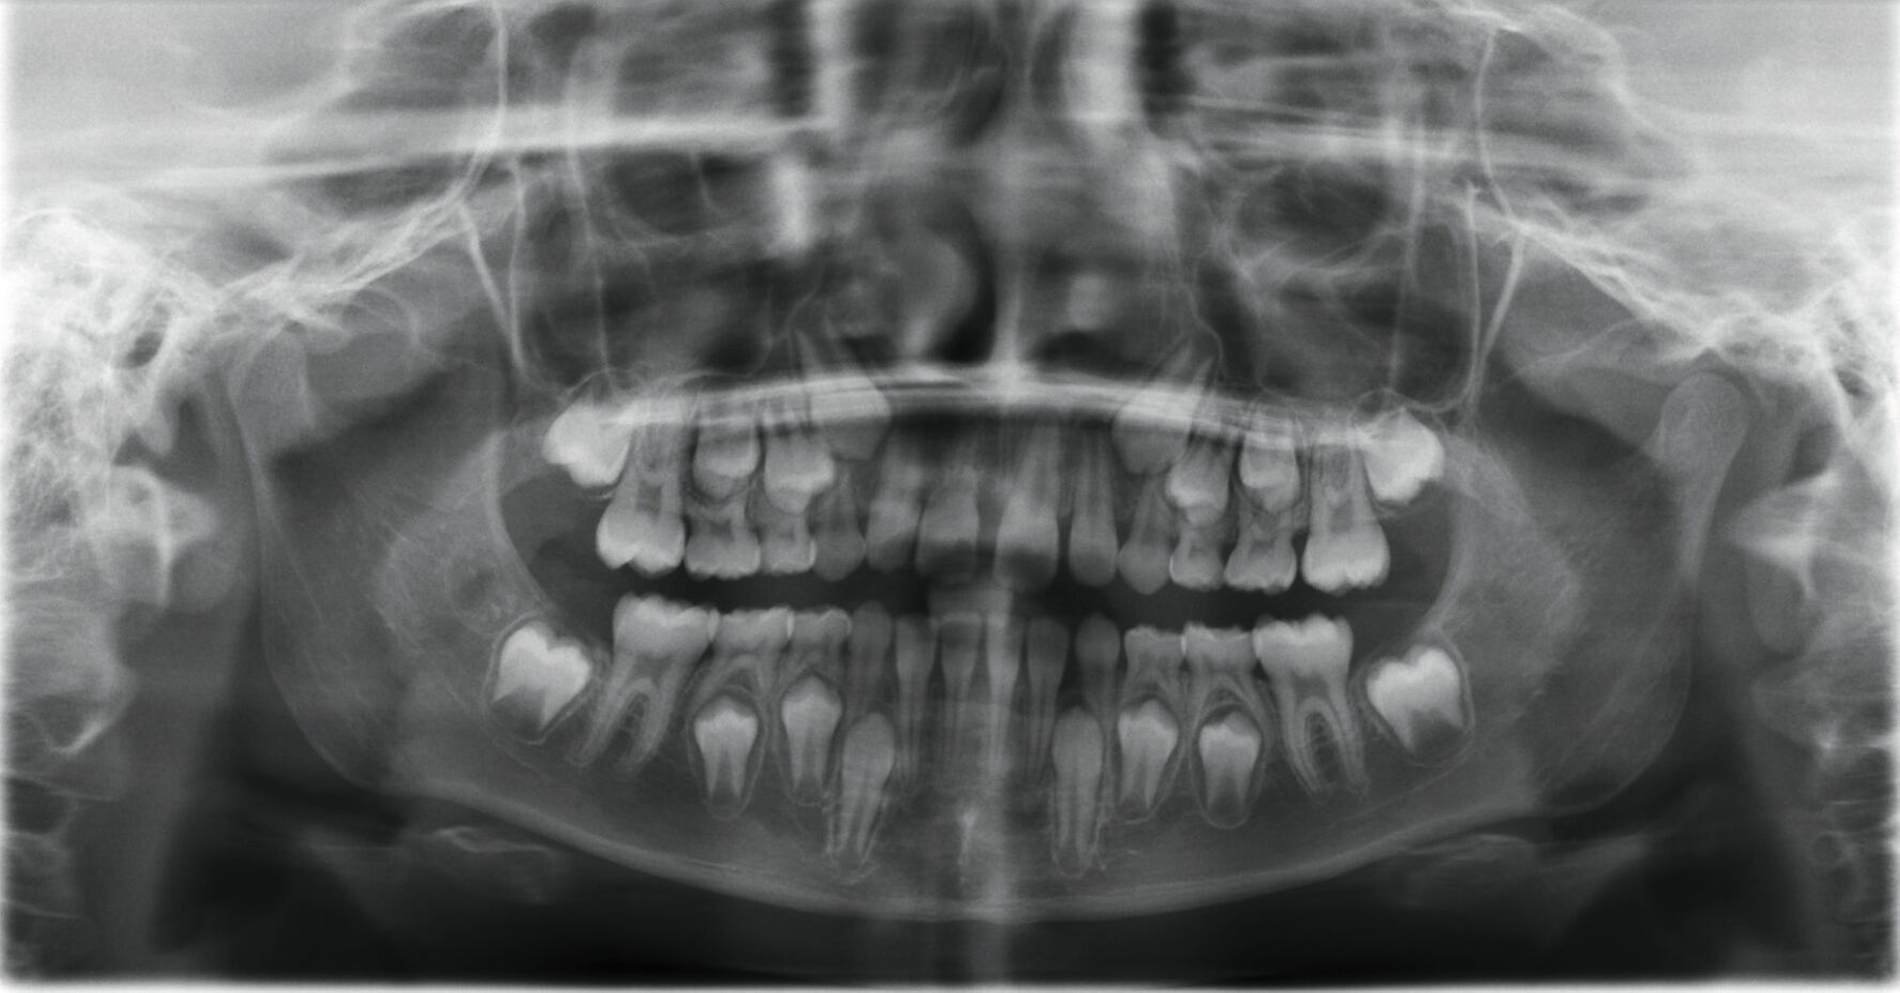

Ein neunjähriges Mädchen hatte bei einem Schlittenunfall den rechten oberen mittleren Schneidezahn verloren. Der Zahn 11 war nach einer extraoralen Lagerungszeit von mehr als 24 Stunden alio loco replantiert und mit einem Titan-Trauma-Splint von Zahn 12 bis 22 geschient worden. Drei Monate nach dem Unfall stellte sich die Patientin mit folgendem Befund vor (Abbildung 2):

Im OPG findet sich nach Replantation mit Pulpotomie (Abbildung 2a) bereits ein vertikaler Einbruch des krestalen Knochens, drei Monate später ist eine infektionsbedingte Resorption des Zahnes 11 erkennbar (Abbildung 2b). Alle vier Milcheckzähne zeigen im Alter von neun Jahren bereits deutlich reduzierte Wurzellängen aufgrund der natürlichen Exfoliation durch die im Durchbruch befindlichen bleibenden Eckzähne. Die Entscheidung fiel auf den Zahn 83 als Autotransplantat, da dieser zu diesem Zeitpunkt die längste Wurzel aufwies (Abbildung 2b).